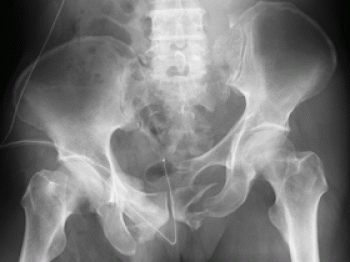

骨盤骨環骨折とは

骨盤骨が形成する環の連続性が骨折によって離断されたものです。

骨折によって骨盤骨の環の連続が離断されても、ある1ヵ所での骨折の場合は比較的に転位は軽度です。

恥骨枝の骨折が、骨盤骨骨折がもっとも多い。

膀胱や尿道の合併損傷がみられる。

骨盤部の著しい変形や、下肢の短縮 がみられる。

骨盤骨環骨折の分類

①腸骨骨折

②仙骨骨折

③恥骨骨折

④坐骨骨折

⑤仙腸関節離開

⑥恥骨結合離開

⑦垂直重複骨折(マルゲーニュ骨折)

垂直重複骨折(マルゲーニュ骨折)とは、恥骨枝や坐骨枝の骨折に、仙腸関節離開や腸骨後部や仙腸が垂直して骨折したもの